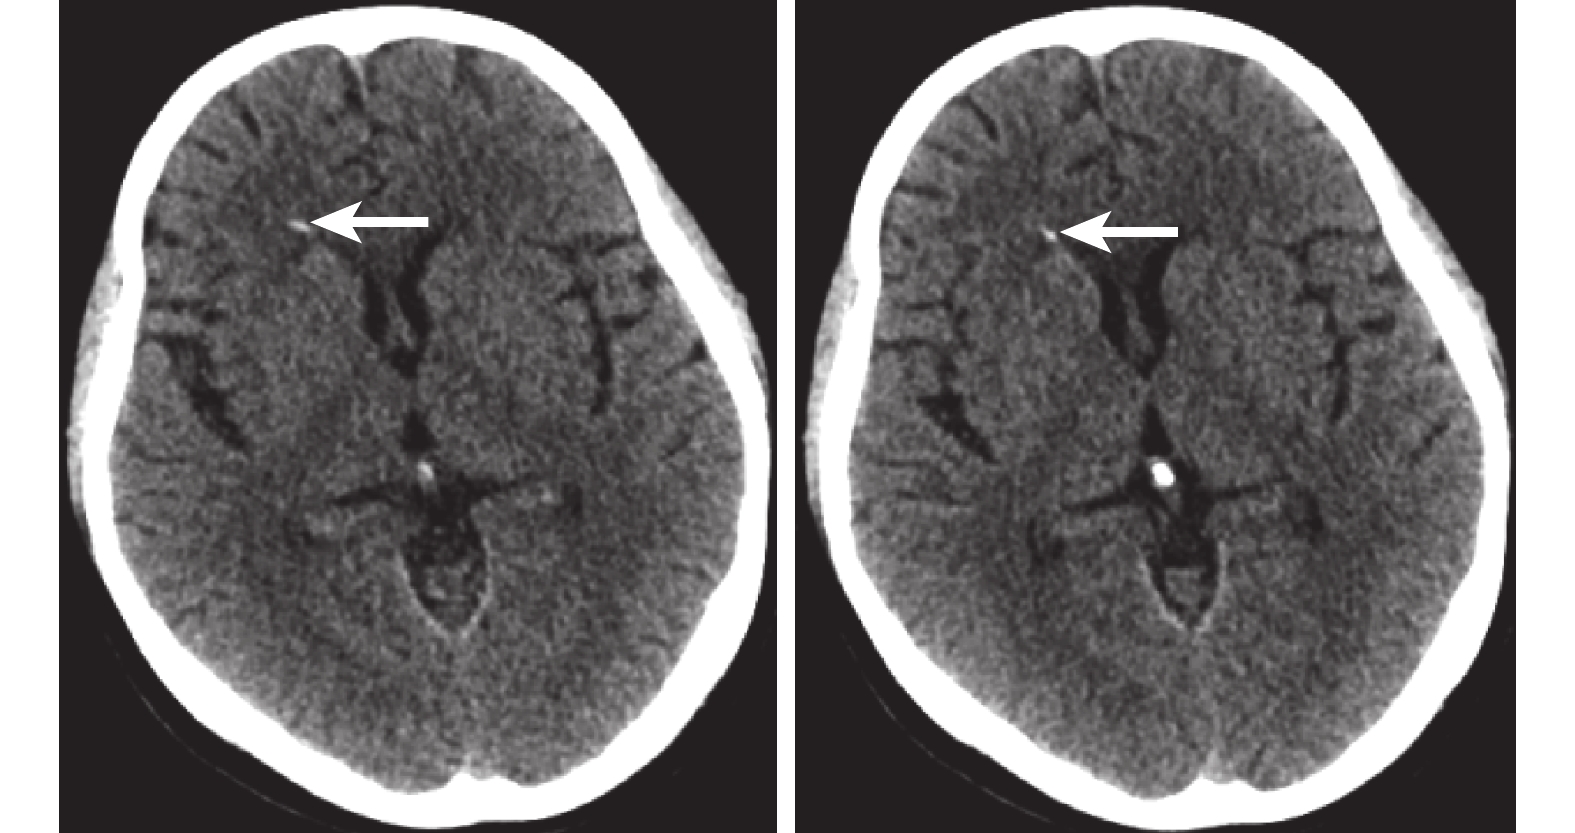

入院查體:T:36.6℃,P:75次/分,R:20次/分,BP:145/85 mmHg。身高158 cm ,體質量63 kg,體重指數:25.2 kg/m2。心肺腹查體未見明顯異常,面神經叩擊征及束臂加壓試驗陰性,神經系統查體未見陽性體征。實驗室檢查:血清鉀3.47 mmol/L、氯105.4 mmol/L、鈉145.3 mmol/L、鈣1.21 mmol/L、磷2.17 mmol/L、鎂0.64 mmol/L、鐵9.90 mg/L,甲狀旁腺激素17 pg/mL,甲狀腺功能、25羥維生素D3未見異常。心電圖示:竇性心律,大致正常心電圖。普通腦電圖示:輕度異常腦電圖。甲狀腺及頸前區淋巴結彩色超聲示:① 甲狀腺全切術后;② 雙側頸前區查見淋巴結,結構未見明顯異常。顱腦計算機斷層掃描(Computed tomography,CT)示:右側側腦室前角旁條狀致密影,鈣化?其他?(圖1)。顱腦核磁共振成像(Magnetic resonance imaging,MRI)示:右側側腦室前角旁見小片狀T1加權成像稍高信號影,T2加權成像、液體衰減反轉恢復序列(Fluid attenuated inversion recovery,FLAIR)呈高信號影,出血?其他?。結合患者病史及輔助檢查考慮繼發性甲狀腺旁腺功能減退,予葡萄糖酸鈣、碳酸鈣、骨化三醇補鈣,復查血清電解質:鉀3.95 mmol/L、氯98.7 mmol/L、鈉139.4 mmol/L、鈣2.18 mmol/L、磷2.10 mmol/L、鎂0.91 mmol/L、鐵11.51 mg/L。病情好轉出院,隨訪4個月患者未在癲癇發作。本研究已通過成都醫學院第一附屬醫院倫理委員會審核批準。

HP的臨床表現是由于兩個主要靶器官:骨骼和腎臟缺乏生理作用。腎臟、大腦和其他軟組織中的鈣化很常見。顱內鈣化在成人和兒童常見,指的是腦實質或血管系統內的鈣化,可分為幾大類:生理性、營養不良、先天性疾病、感染性、血管性、腫瘤性、代謝性、炎癥性和毒性疾病[4]。生理性鈣化通常見于松果體、脈絡叢、大腦鐮和小腦幕[5-6]。甲狀旁腺機能減退癥大腦鈣化影響最顯著的是雙側基底節,最常見的是蒼白球。齒狀核、放射冠、皮質下白質和丘腦可能發生鈣化,鈣化現被認為是由長期高磷血癥引起的,但確切的病因尚不清楚[7-8]。本例中顱內鈣化見于右側側腦室旁,鈣化不明顯,考慮和病程短有關。